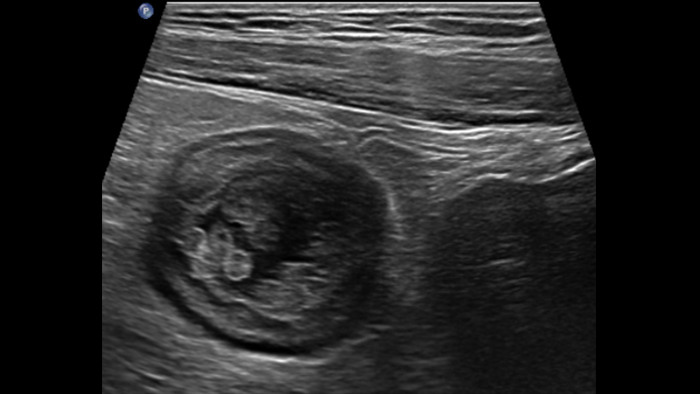

Dans le cas de la rectocolite hémorragique, en présence d’une forme grave et aiguë, la paroi est parfois plus épaisse. Ici, l’épaisseur des couches sous-muqueuse et muqueuse est augmentée en raison d’un œdème, tandis que la couche musculaire reste normale. En cas de forme chronique tardive, des pseudopolypes sont visibles à l’intérieur du lumen, ce qui n’a jamais été décrit à ma connaissance.

Late form pseudopolyps

Dans le cas de la forme aiguë de la rectocolite hémorragique, la technologie MFI met en évidence un grand nombre de vaisseaux dans la paroi, mais également dans le tissu adipeux adjacent. Dans le cas des pseudopolypes, des vaisseaux peuvent parfois s’y développer.

UC pseudo-polyps